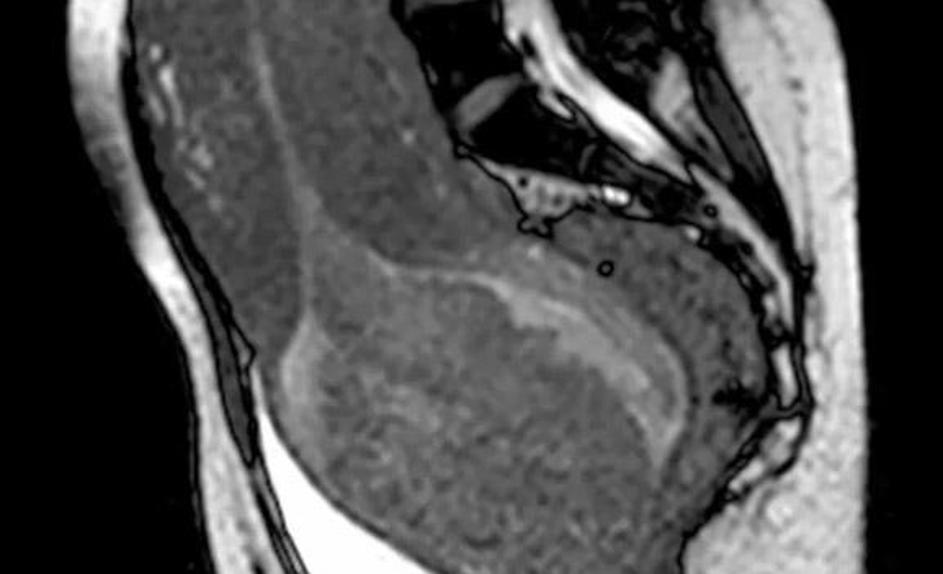

porod, snemanje, magnetna resonanca Poporodni pogled v notranjost maternice brez placente. Žurnal24 porod, snemanje, magnetna resonanca